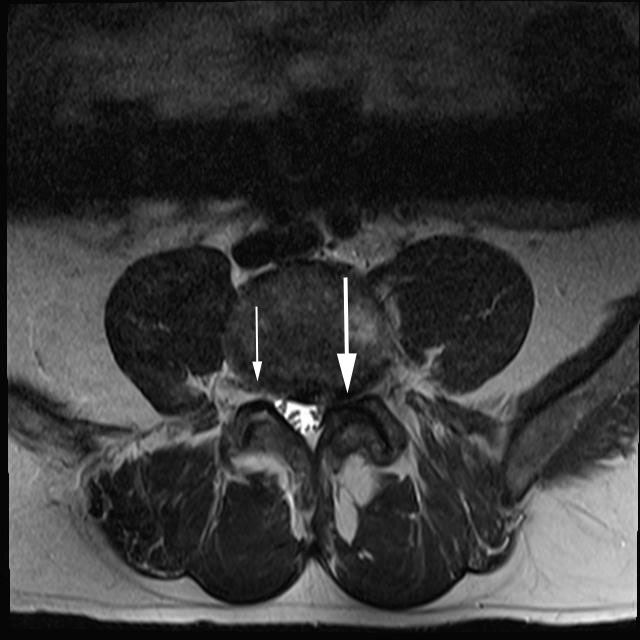

Case Of Grade 1 Foraminal Stenosis In Transverse Direction T1